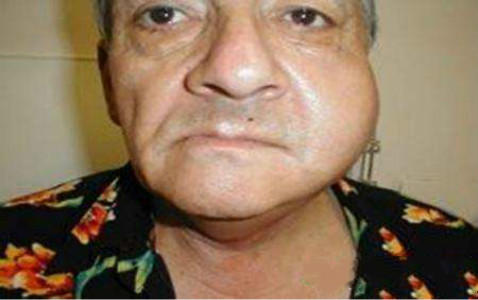

慢性淋巴結炎圖片

慢性淋巴結炎 (8)

慢性淋巴結炎 (9)

慢性淋巴結炎 (6)

慢性淋巴結炎 (7)

慢性淋巴結炎 (45)

慢性淋巴結炎 (46)

慢性淋巴結炎 (47)

慢性淋巴結炎 (48)

慢性淋巴結炎 (49)

慢性淋巴結炎 (5)

慢性淋巴結炎 (50)